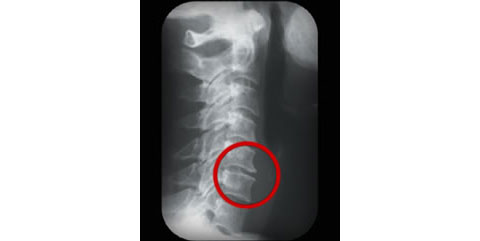

首先,骨刺是指「骨質增生」,意思是在原有的骨骼上長出新的骨。其主要原因包括是脊椎因年紀漸長而開始退化,另外是姿勢不良。結構上,我們的脊柱如果從側面看,天生是有3個弧度的。頸椎和腰椎的弧度是向前凸,而胸椎則是向後凸。脊椎的其中的一個作用是力學上支撐身體重量,這些弧度令身體重量得以平均分配。長時間姿勢不良可以令以上弧度改變,例如弧度被拉直、倒轉或過多。當弧度出現改變,脊椎骨便會變得不穩定令重量分配不平均。在不穩定的狀態下,如果脊骨某些位置長時間受力,壓力比正常大,該位置便可能會開始增生。時間長了骨質增新更可能呈尖銳型狀,所以俗稱「骨刺」。

骨刺很常見地出現於脊椎骨的前方,由於脊椎的前方神經線不多,即使骨刺出現亦未必會引致痛症。反觀脊椎關節後方兩側是神經線出口,如果骨刺生長在神經線出口邊緣便有機會刺激神經線從而引致痛症。除了痛症外更可能引致手腳麻痺、無力等複雜症狀。

基於以上理由,出現骨刺並不代表一定會有症狀,反已要視乎骨刺出現的位置。但就個人所接觸的案而言,骨刺出現多數代表脊椎已出現不同程度的問題並已經累積多年。頸背痛有很多原因,例如脊椎位、椎間盤突出和 肌肉拉傷發炎等,骨刺並不一定是唯一的解釋。另外要留意的是,骨刺不再是老人家的「專利」。很多20-30歲的痛症患者都有骨刺的出現。原因大多是姿勢不正例如「低頭族」、長時間坐和欠缺運動等。

骨刺存在與否是必須靠客觀檢查例如X光去判斷的,不能單靠用臨床檢查判斷。如有懷疑應盡早向專業人士查詢和檢查。